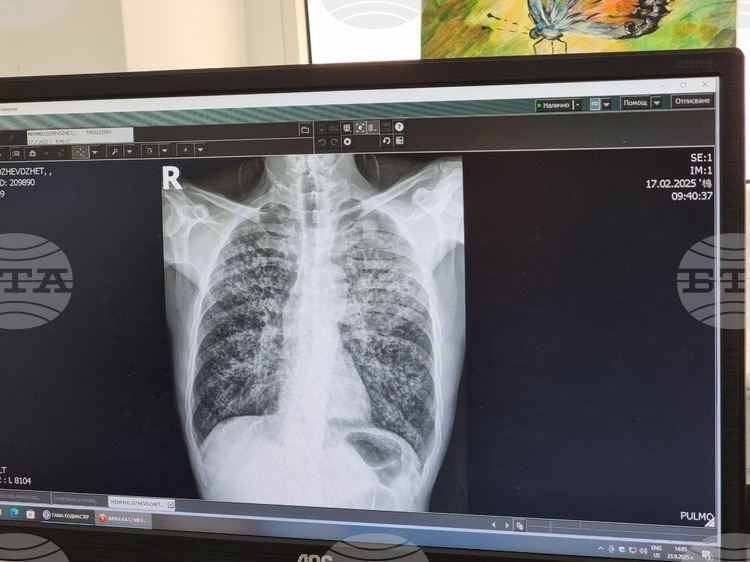

Университетска болница „Д-р Георги Странски“ в Плевен стартира инициатива за безплатна оценка на риска от белодробна туберкулоза. Кампанията ще бъде проведена в периода от 8 до 12 декември, като прегледите ще се извършват между 12:30 и 14:30 часа в отделението за диспансерно наблюдение на пневмо-фтизиатрични заболявания. За оптимално организиране на процеса, записването за прегледи трябва да се направи предварително, като това може да стане на място или чрез обаждане на телефон 064/802 994.

Участието в кампанията не изисква заплащане и е отворено за всички, без значение от техния здравноосигурителен статус. Участниците ще преминат през анкети, медицински прегледи и консултации със специалисти. При необходимост ще бъдат извършвани и допълнителни медицински изследвания.